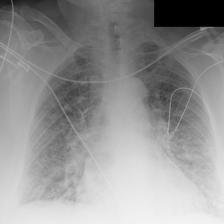

We found that many lateral acquisitions in the dataset were unexpectedly labelled as frontal (Figure 7(a)). Some images contained only noise (Figure 7(b)), non-human samples (Figures 7(d) and 7(e)) or incorrect anatomy (Figure 7(g)). Often, acquisitions with an incomplete field of view (FOV) (i.e., the lungs are not completely visible) were repeated (Figure 7(c)). Lastly, post-processed images were detected by the algorithm such as contrast-enhanced scans (Figure 7(i)) that are not often used for diagnostic purposes in clinical practice.

Curation of imaging datasets

CXR datasets [36] often contain multiple image acquisitions in a single visit due to data quality issues such as a limited field-of-view or scanning the wrong body part (Figure A.7). Unlike [9, 32, 81], we conduct curation to choose higher quality images among the potential candidates instead of performing a random selection. For this step, a separate BioViL-T is trained on ‘clean’ studies with single acquisitions and later used in a zero-shot setting to detect out-of-distribution samples [26, 27] arising from the re-imaging process. The candidate is selected as follows: for a margin . This approach is applied to enhance the quality of the temporal classification dataset given its limited size.